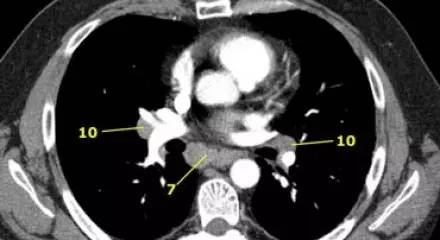

肺 CT 横断面上的隆突下淋巴结(7)、肺门淋巴结(10)